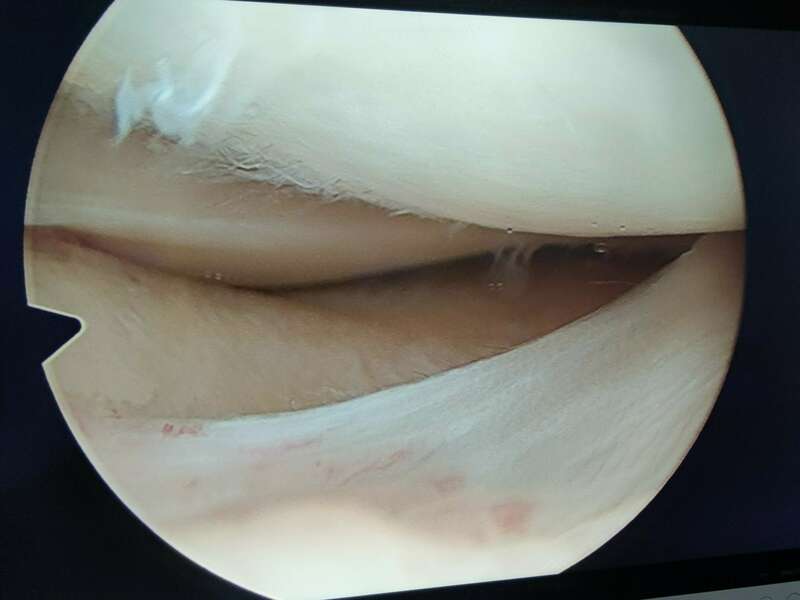

La plupart du temps, les lésions méniscales traumatiques sont traitées chirurgicalement. Deux gestes sont possibles : la réparation méniscale et la méniscectomie. Ces deux interventions sont réalisées au cours d’une arthroscopie et ont des indications spécifiques à chacune.

Nous différencions trois zones. Une « rouge-rouge », au contact de la capsule articulaire (en périphérie), bien vascularisée, qui peut être suturée, surtout chez le jeune. Une zone « rouge-blanche » médiane, qui est moins cicatrisable, car moins bien vascularisé. Et une zone « blanche-blanche » (en profondeur), faiblement vascularisée, et par conséquent rarement suturée.